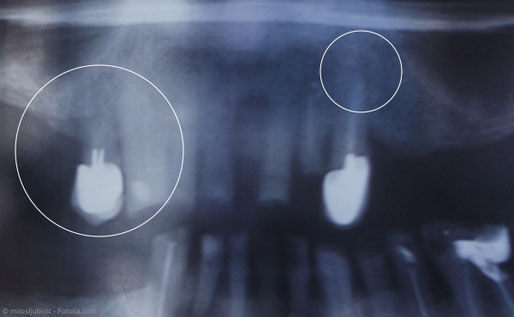

Unvollständige Wurzelfüllung (links) und Entzündung an der Wurzelspitze trotz Wurzelfüllung (rechts). Was kann man tun?

Wegen stark gekrümmter Wurzelkanäle gelang es dem behandelnden Zahnarzt nicht, die Kanäle in ganzer Länge aufzubereiten, zu reinigen und zu füllen. Die Entzündung an der Wurzel besteht weiterhin.

Bei der vorangegangenen Wurzelbehandlung wurde ein Kanal übersehen und deshalb nicht aufbereitet und gefüllt. Die Bakterien in diesem Kanal erhalten die Entzündung aufrecht.